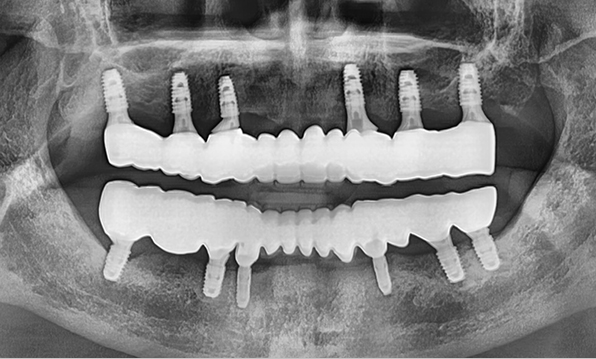

위 아래 치아가 정확하게 맞아야하는 고난이도 임플란트

임상 경험이 많은 숙련된 전문의의 섬세한 기술력이 중요합니다.

3D 디지털 진단을 통한 체계적인 계획

전체 임플란트는 위턱과 아래턱의 교합, 잇몸뼈의 상태 및

얼굴 변화 등 모든 것을 고려해 식립해야 합니다.

서울더자연치과는 3D 디지털 기술의 정밀 진단을 바탕으로

수술 계획을 세워 수술을 집도합니다.

치료기간 : 2021.04.12~2021.09.15